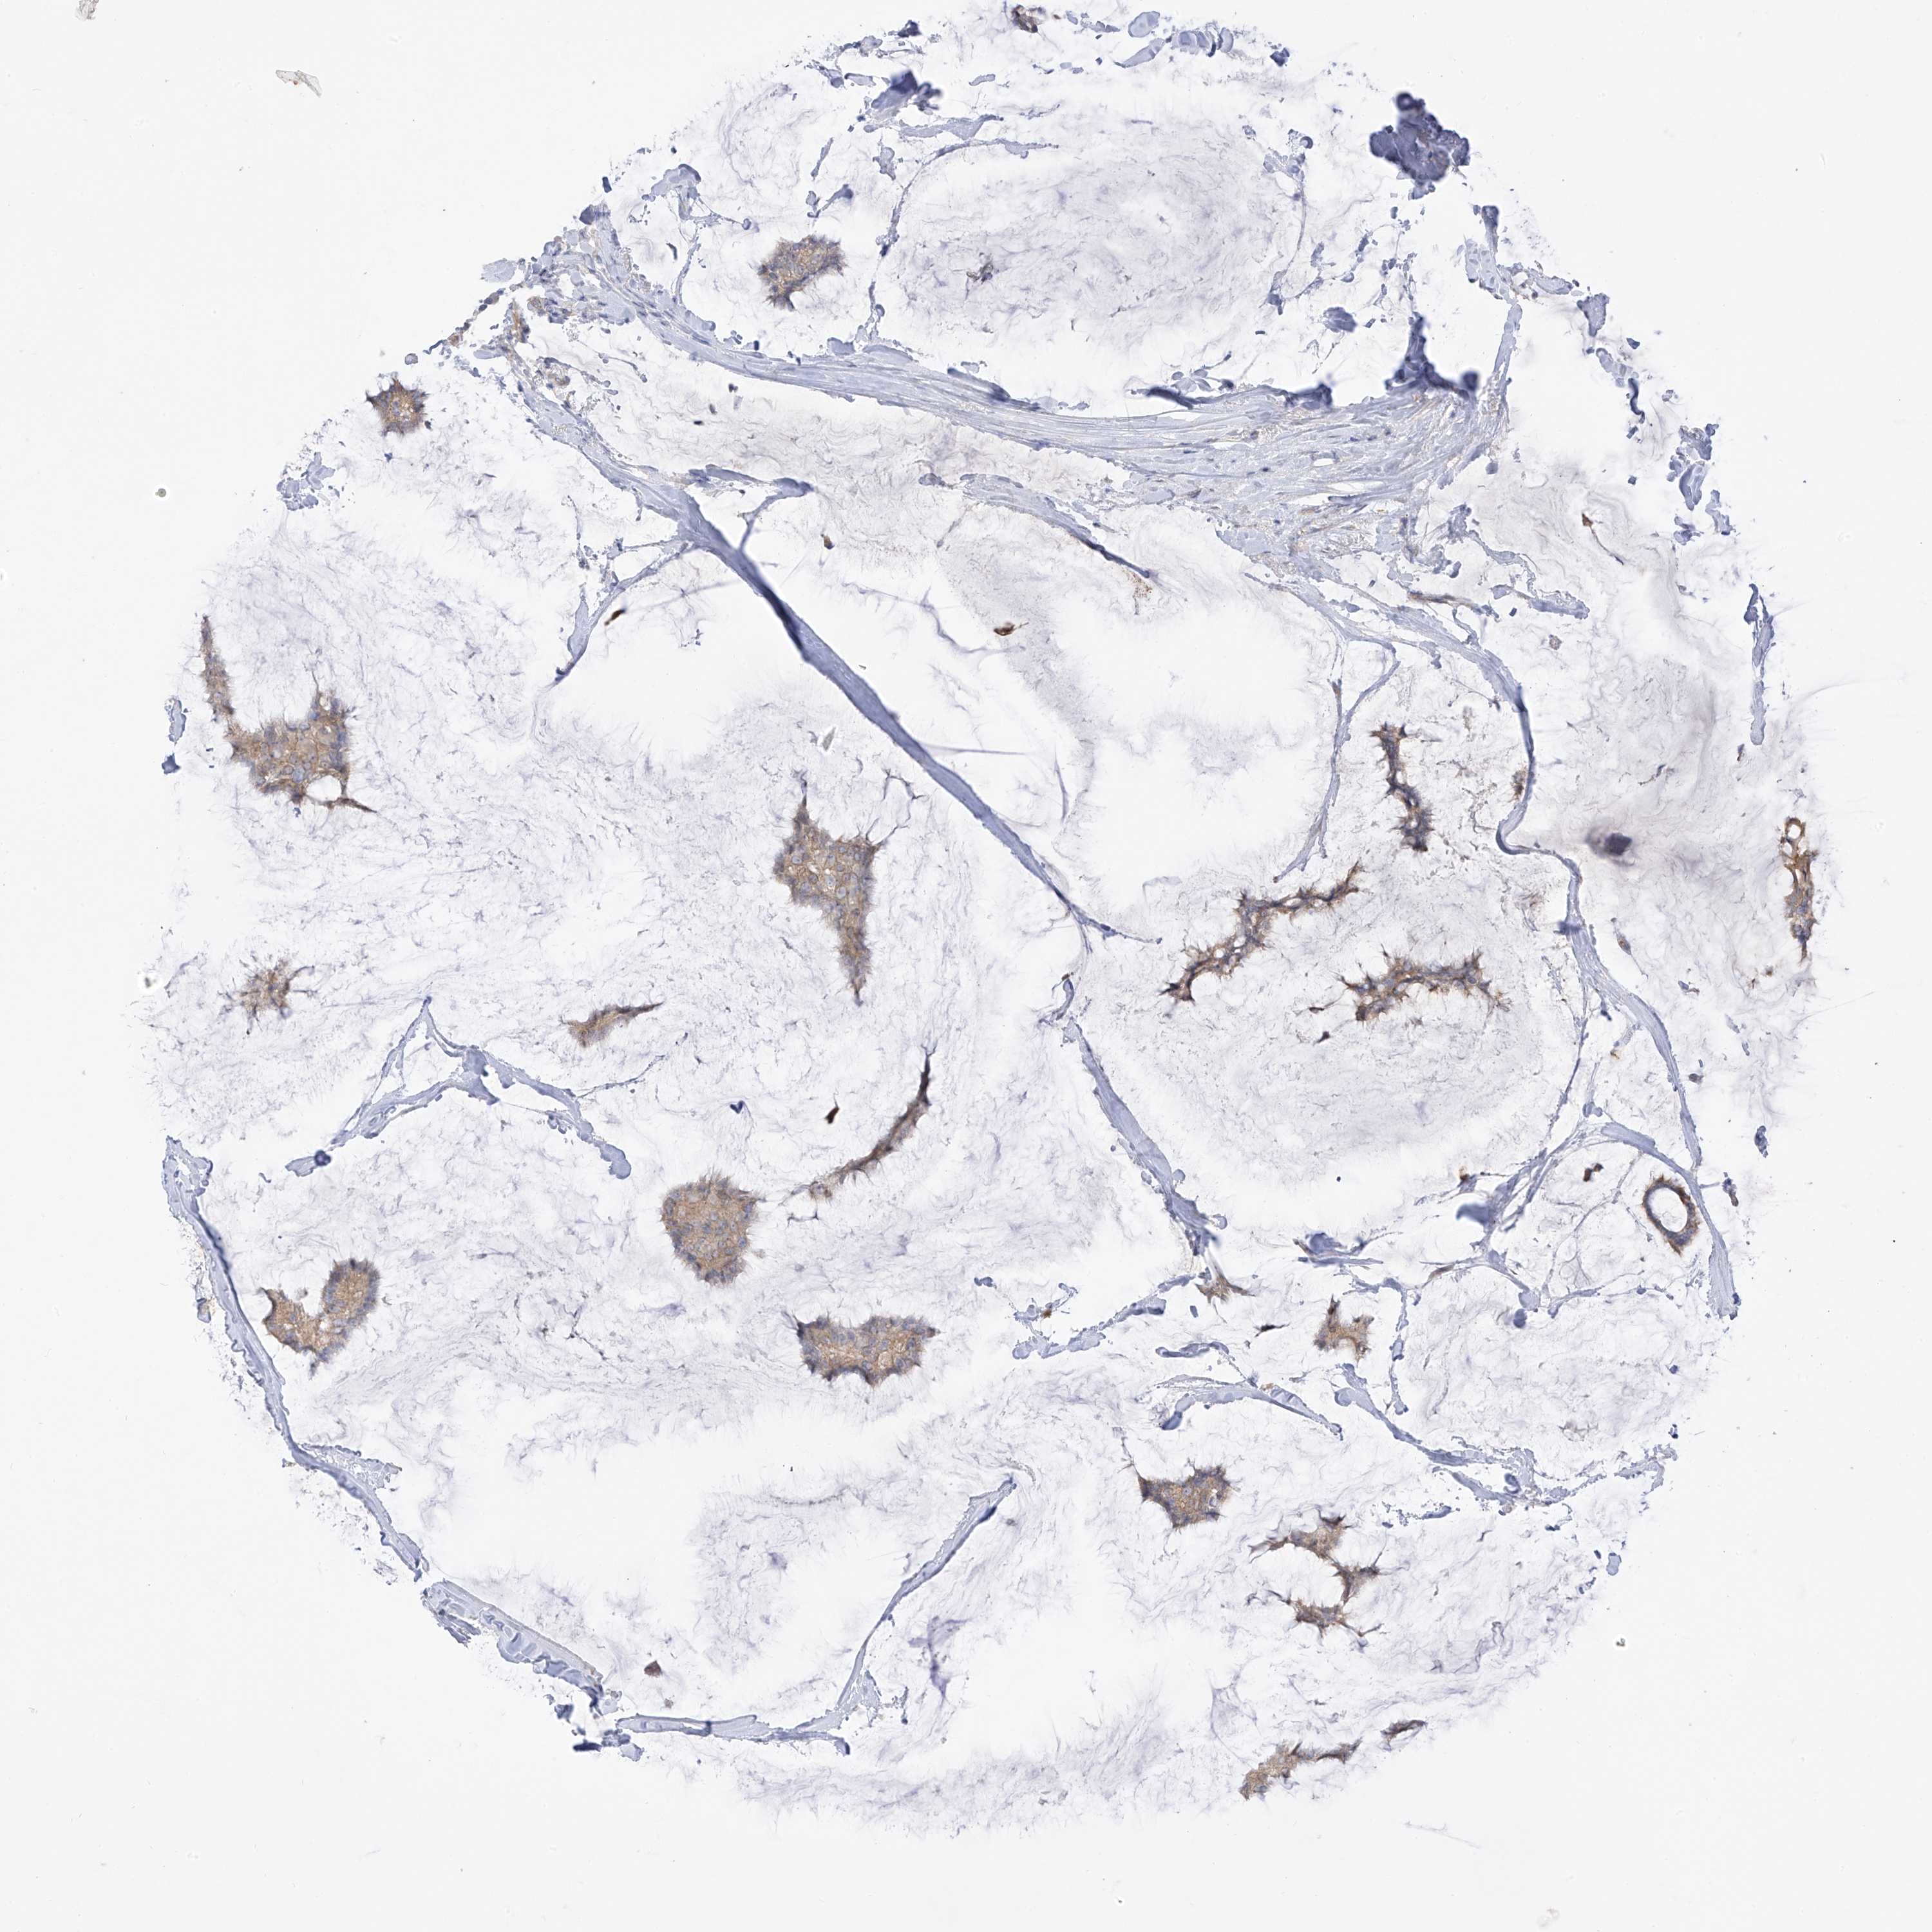

Breast cancer

Human cancer